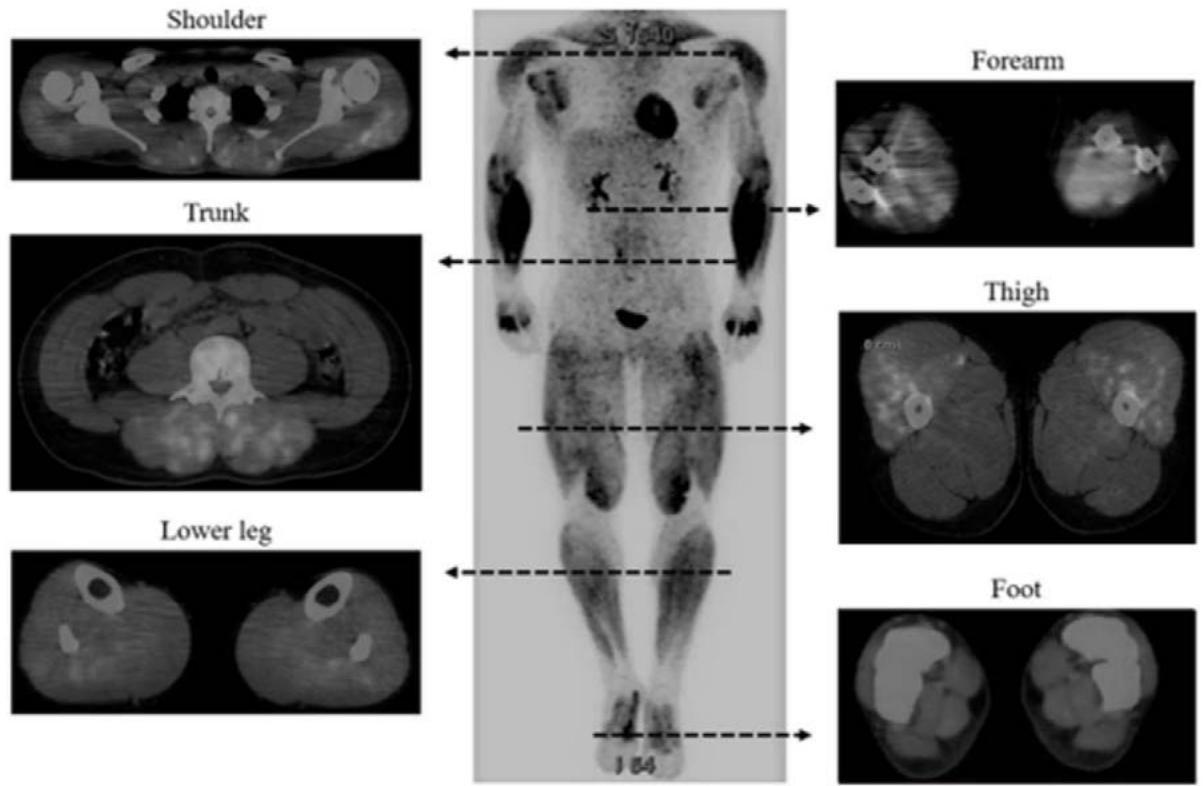

Following our line of thought on hypoxia we would like to add data related to exercise. Exercising subjects can develop hypoxemia (235, 236) and physical activity can lead to HIF activation in skeletal muscle (237). Experimental hypoxia in skeletal muscle of rabbits is accompanied by a reduction of the levels of ubiquinone (130). A decrease of the $\mathrm{CoQ}_{10}$ levels is seen together with diminished ATP levels in isolated rabbit ventricles under hypoxia (Table 2 in (131)). Metabolic changes related to exercise can be seen with diagnostic $^{18}$ F-FDG imaging. Nakase et al., demonstrated focal uptake in football players (238) (Figure 9).

Whole Body Muscle Activity during the FIFA 11+

Figure 9: Taken from Nakase J, Inaki A, Mochizuki T, Toratani T, Kosaka M, Ohashi Y, et al. Whole Body Muscle Activity During the Fifa 11+ Program Evaluated by Positron Emission Tomography. PLoS One (2013) 8(9):e73898. Epub 2013/09/26. doi: https://doi.org/10.1371/journal.pone.0073898. License: Creative Commons Attribution License

doi:10.1371/journal.pone.0073898.g002

Figure 2. Representative whole-body positron emission tomography images after performance of the $11+$ by patients in the exercise group.

Tracer uptake can be more intense according to the intensity of exercise such as weightlifting as shown by Yoshimizu et al., in 2022 (239). Not only the muscle involved in weightlifting but also the heart showed intense tracer uptake (figure 10) revealing the systemic dimension of exercise.

Figure 10: Taken from Yoshimizu R. Whole Body Muscle Activity During Weightlifting Exercise Evaluated by Positron Emission Tomography (2022). Available from: https://www.researchsquare.com/article/rs-612816/v2. License: CC BY 4.0 Figure 2

#### Representative whole-body PET images after performance of HPC

Representative whole-body PET images of the HPC group are shown. SUVs were significantly increased in 29 of 71 skeletal muscles in the whole body. PET; positron emission tomography, HPC; hang power clean